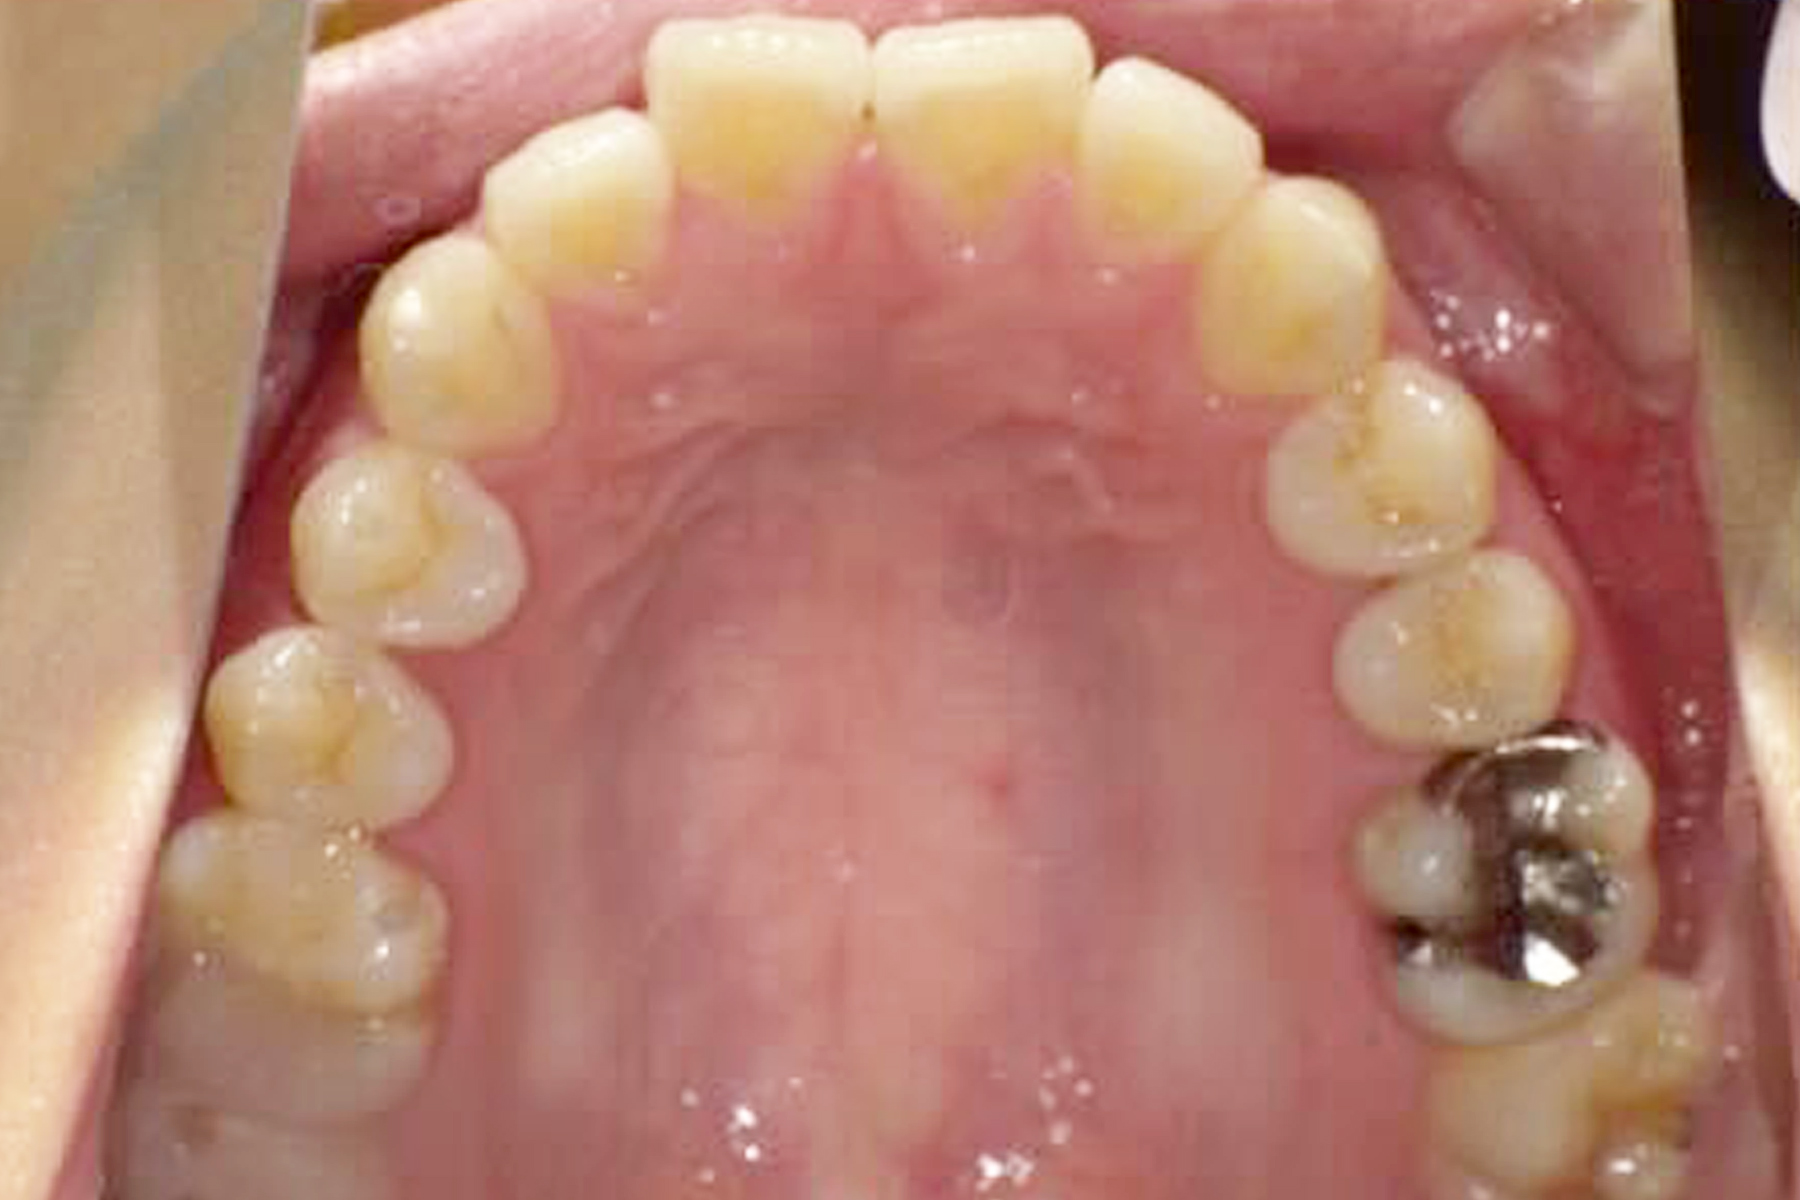

Case.1

BEFORE

AFTER

| 担当医 | 林 大貴 |

|---|---|

| 主訴 | 歯並びを直したい |

| 期間 | 約6ヶ月 |

| 費用 | 550,000円 |

| 治療内容 | マウスピース矯正 |

| 治療に伴うリスク | 動的治療後、保定装置を決められた期間確実に装着しなかったり した場合後戻りが起こる可能性があります。 |